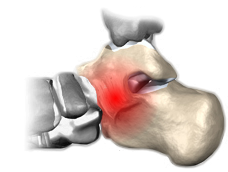

Coalizão Talocalcaneana

A coalizão talocalcaneana é a fusão entre o calcâneo e o tálus.

Podemos encontrar a barra óssea na articulação posterior, média e anterior do calcâneo com o tálus; mas a faceta média é a mais acometida.

A dor e a rigidez tornam-se importantes por volta dos 12 anos de idade.